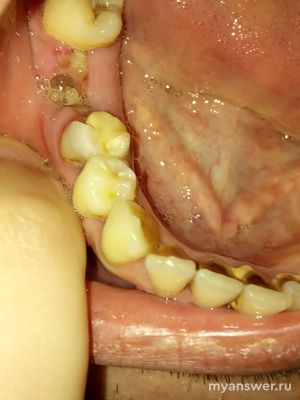

Сможете определить по фото удалил ли стоматолог корни зуба?

На представленном фото полости рта в лунке удалённого зуба присутствует фибринозный налёт на раневой поверхности, а значит зуб удаляли не сегодня, и не вчера. Цвет и вид фибринозного налёта внешне напоминает остатки корней в лунке. Для определения оставшихся корней после удаления зуба(а вдруг) нужен рентген снимок. Ещё, оставленные корни после удаления зуба можно определить своим языком, после того, как ватку из-рта выплюнешь. В моей жизни такой факт был. Недалеко отошёл от стомат поликлиники, языком оставленный корень удалось нащупать, пришлось вернуться для до удаления. А в данной ситуации можно сделать только рентген, а корень(если вдруг) удалять уже после заживления лунки бывшего зуба.